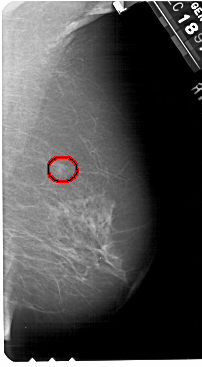

A_1528_1.LEFT_MLO

FILE: A_1528_1.RIGHT_MLO.OVERLAY

TOTAL_ABNORMALITIES 1

ABNORMALITY 1

LESION_TYPE CALCIFICATION TYPE PLEOMORPHIC DISTRIBUTION CLUSTERED

LESION_TYPE MASS SHAPE IRREGULAR MARGINS ILL_DEFINED

ASSESSMENT 4

SUBTLETY 3

PATHOLOGY MALIGNANT

TOTAL_OUTLINES 1